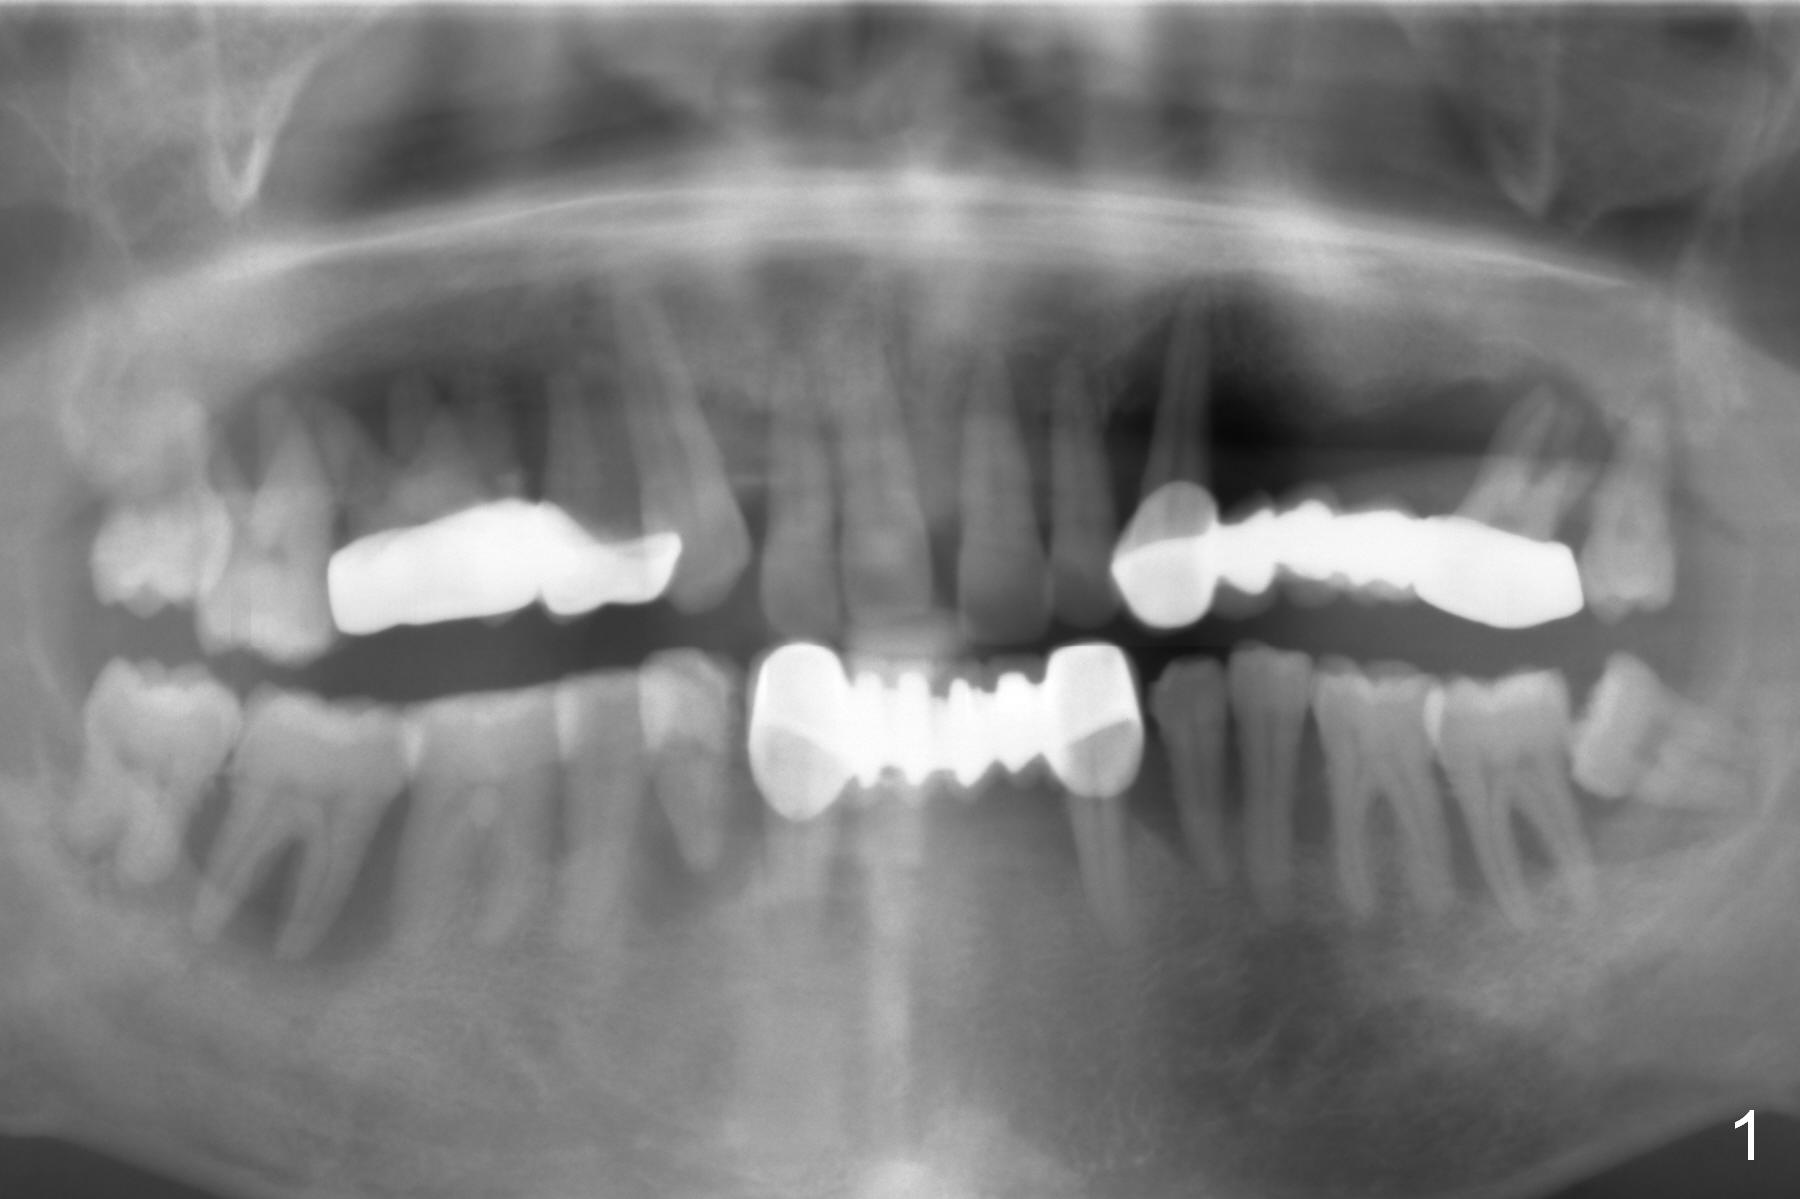

A 45-year-old man has advanced periodontitis and bruxism (sufficient remaining bone height, Fig.1).  Full mouth restoration will be done by quadrant with preservation of a few of relatively healthy teeth.  The 1st quadrant to be treated will be the upper left (Fig.2).  The teeth #9-11 and 15 will be extracted (Metronidazole) with immediate implants.  A delayed implant will be added at #13 for #11-15 bridge (Fig.4).  In addition to the large radiolucency around the roots of #9 and 10 (Fig.3 red dashed line), the gingiva at #11 and 15 is excessively thick (red arrows).  For example at #11, a long implant has to be placed a little more outside the bone (Fig.4 green area), since the longest cuff of the abutment (red area) is 5 mm for UF implant system.  The longer the cuff, the less amount of the implant will be outside the bone with less chance of periimplantitis.  When the coronal implant threads are exposed, a large amount of bone graft has to be placed (Fig.4 yellow circles).